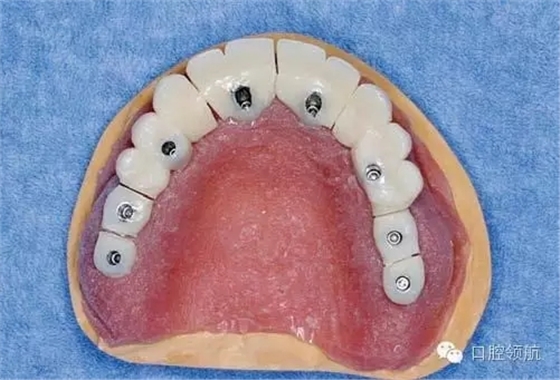

醫(yī)生在制作即刻負重的上部結構時,應把事先做好的臨時上部結構(圖3)先分割開(圖4),再在口腔內分幾次用快速聚合樹脂連接(圖5)。

圖4 先把做好的臨時上部結構全部分割開。

圖5 在口腔內分幾次用快速聚合樹脂連接。

各個連接部位,首先在牙頸部連接固定,充分硬化后再向牙冠方擴大固定范圍,如此逐漸連接固定,切勿一次連接,要逐漸補償聚合的收縮而操作,因為最終合計的硬化收縮量相當大。